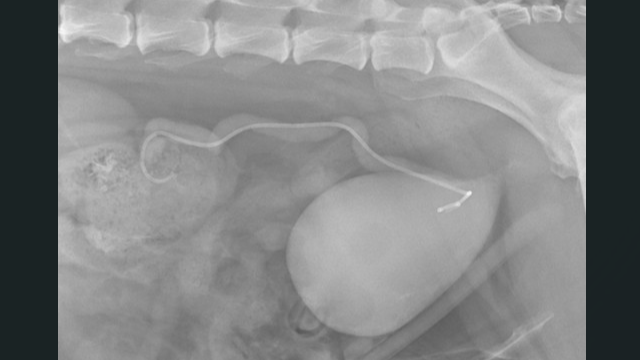

A patient was referred to Austin Veterinary Emergency & Specialty Center (AVES) for management of urinary obstruction caused by urothelial carcinoma. Initial evaluation included a positive BRAF test and imaging that revealed a prostatic mass extending into the urethra, resulting in obstruction at the left ureterovesical junction.

Radiology (Dr. Price): Provided ultrasound guidance for IV catheter placement into the left renal pelvis, confirming moderate to severe dilation of the left renal pelvis and ureter.

Surgery (Dr. Fleming): Passed a guidewire from the left kidney, through the ureter, into the urinary bladder.

A 3.7 Fr fenestrated ureteral stent was positioned percutaneously from the renal pelvis to the bladder, successfully bypassing the tumor-associated obstruction without surgical incisions.

No intraoperative or postoperative complications occurred. Postoperative imaging confirmed ideal stent placement, and the patient demonstrated appropriate urine output.